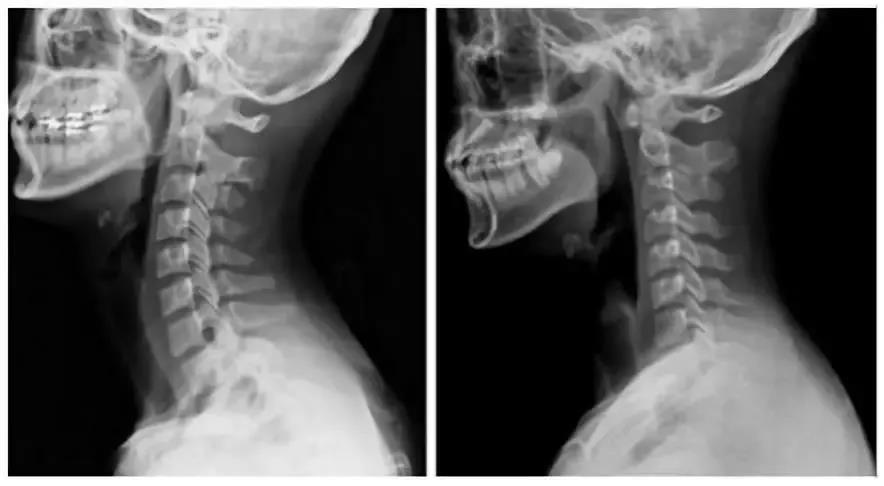

因长时间低头、过度疲劳或颈部着凉而发病。X线显示颈椎生理曲度变直或反弓,椎体边缘增生,椎间隙轻度变窄。表现为颈部僵硬疼痛,活动受限。